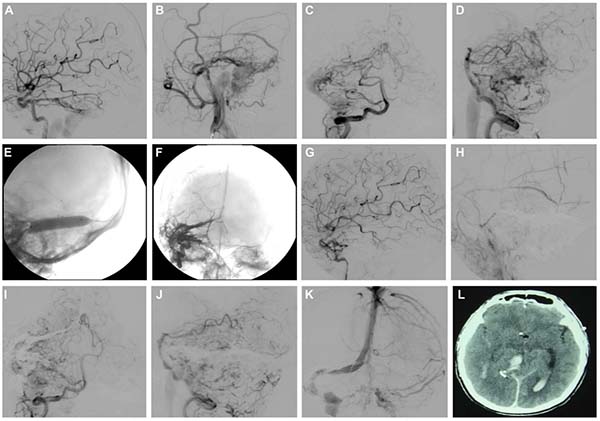

图1. A-D:对颈内动脉、颈外动脉及椎动脉行DSA显示一例由多支“纯”软脑膜动脉及硬脑膜动脉供血的Borden I型DAVF。供血动脉包括脑膜垂体干、大脑中动脉的“纯”软膜分支、枕动脉、脑膜中动脉、以及来自后循环的分支如大脑后动脉、小脑上动脉和小脑前下动脉。该患者有静脉窦支架植入病史,动静脉瘘正好位于原支架植入位置。此外,在后循环的软膜供血动脉中观察到与血流相关的动脉瘤。E-H:通过脑膜中动脉入路,在静脉途径球囊保护下使用Onyx完成瘘口的完全闭塞,未对任何PAS进行栓塞。I和J:完全栓塞后即刻行椎动脉造影,未见异常。K:静脉晚期显示患侧横窦-乙状窦仍保持通畅。L:术后患者保持意识清醒、反应良好,但返回病房后突发呼吸骤停。紧急头颅CT显示右侧颞叶出血,并伴有脑室内出血。

图2. A和B:术前椎动脉造影;C和D:术后即刻椎动脉造影;E和F:术后出现颅内出血后的即刻复查造影。与先前影像相比,可见一来自PAS的异常扩张结构(红色箭头所示),提示其可能与此次颅内出血有关。

视频1:该病例与图1和图2相对应,显示在DAVF未完全闭塞前,由疑似未闭塞的“纯”软膜动脉供血引发的出血性并发症。视频链接:https://www.dropbox.com/scl/fi/3jyylsdxcqapvf0z9lbld/Video1.mp4rlkey=q8jk8rjxv73e1em3ytuy4ml3w&e=1&dl=0(可点击文末”阅读原文“查看)